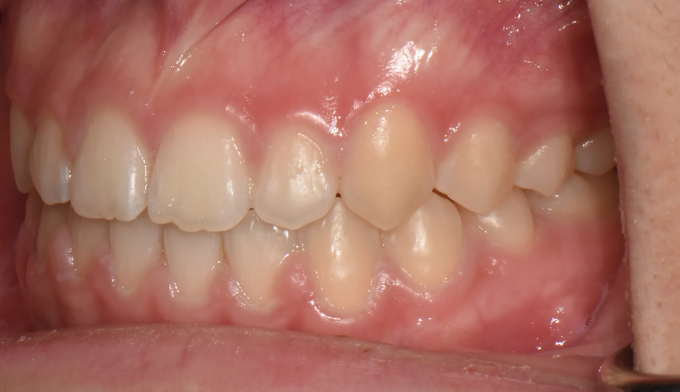

개방교합은 좋지않은 발음을 만들기도 하지만 심미적으로도 좋아보이지 않아서 교정치료를 받으러 많이 오십니다. 치아는 가지런하므로 교정치료가 어렵지 않아 보이지만 개방교합의 치료는 교정용 미니스크류의 식립도 필요하며, 재발도 잘되는 어려운 교정입니다. 교정치료 이후에 재발되지 않게 주기적인 관리 및 연습도 필요합니다.

어금니의 미니스크류의 식립을 통하여 개방교합을 치료하였습니다. 총 치료기간은 13개월입니다.